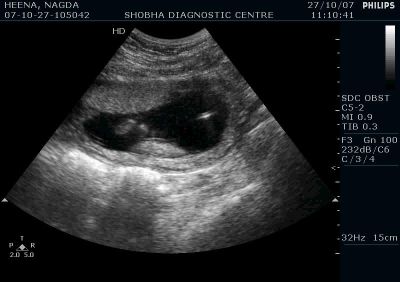

Prenatal Diagnostic Procedures

Following PRENATAL DIAGNOSTIC PROCEDURES are performed at shobha diagnostic centre:

Systematic fetal sonography is the first step in detecting and diagnosing the birth defects, however to diagnose chromosomal abnormalities and certain hereditary syndromes more advanced tests are needed.